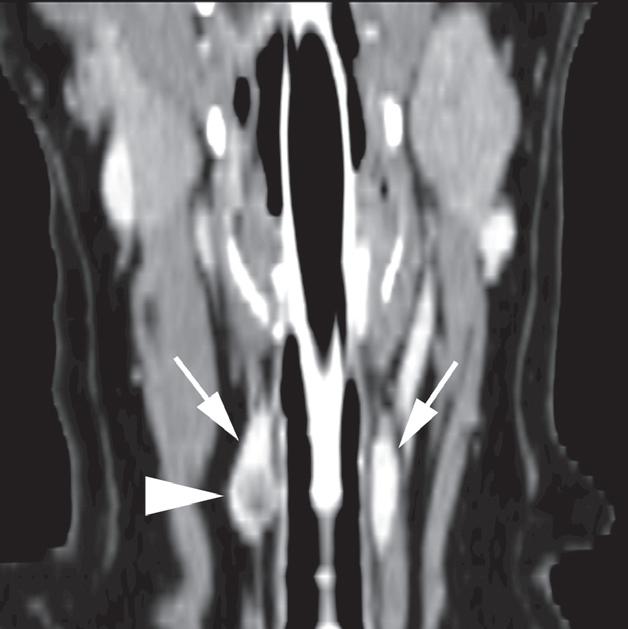

Badanie wykonano u 12-letniej, kastrowanej samicy owczarka australijskiego z prawostronną masą w dobrzusznej części szyi. Badanie USG wykazało dużą, litą, unaczynioną masę w obrębie prawego płata tarczycy (a) oraz mniejszą, hipoechogeniczną masę w obrębie lewego płata (b). Obrazy TK przed i po podaniu środka kontrastowego (c–f) ułożone od doczaszkowych do doogonowych ukazują dużą, prawostronną, jednorodnie wzmacniającą się masę (c–f – duża strzałka) z niewyraźną granicą dobrzuszną oraz pozatorebkowym szerzeniem się i rozlanym wzmocnieniem pokontrastowym przyległych tkanek (e, f – grot strzałki). W obrazie bardziej doczaszkowym widoczny jest prawidłowy lewy płat (c, e – mała strzałka), natomiast w obrazie bardziej doogonowym jest on powiększony i ma niższą gęstość, niż można by oczekiwać, co sugeruje obecność drugiej, mniejszej masy (d, f – mała strzałka). W obrazach reformowanych wzdłuż osi długiej widać dwa małe guzki w lewym płacie (h – małe strzałki). Wyniki obrazowe potwierdzono podczas zabiegu (i, j – strzałki). Biopsja wycinkowa wykazała prawostronnego raka tarczycy z naciekaniem pozatorebkowym oraz lewostronnego gruczolaka tarczycy